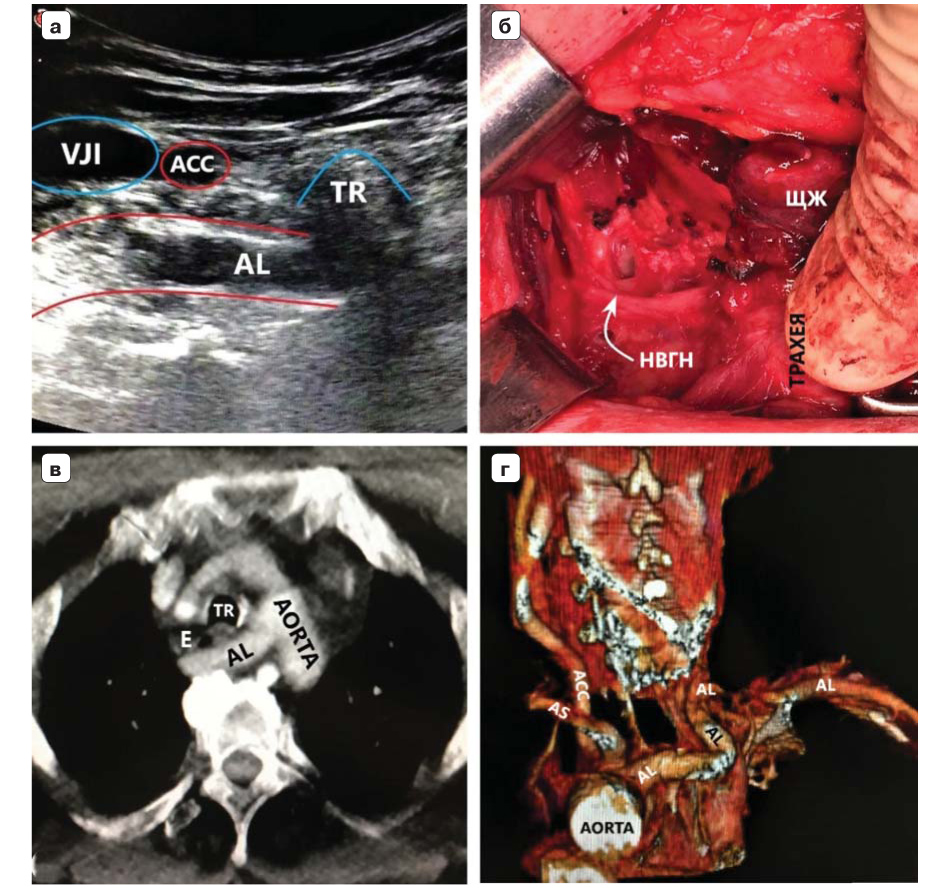

6. Fig. 3. The patient is 58 years old, BMI - 21.7. a - color duplex scanning of the vascular bundle of the right half of the neck with a linear sensor at the level of the right sternoclavicular joint. The right common carotid artery was traced to the place of “intersection” with the trachea (no BCC was detected). AL is located at a considerable distance from the right common carotid artery. b - intraoperative picture. Type I NVGN (according to Avisse – Toniato) has a downward direction and consists of two branches (arrows). c - axial CT scan with angiography of the vessels of the aortic arch. AL is located behind the trachea and esophagus. d - computer three-dimensional reconstruction demonstrates AL syntopia with a common carotid artery. AL is the last, fourth branch of the aortic arch. ACC - arteria carotis communis dexter, TR - trachea, E - esophagus. VJI - vena jugularis interna dexter, NV - nervus vagus dexter. | |

2. Fig. 2. The patient is 32 years old, body mass index (BMI) - 18.5. a - ultrasound of the vessels of the upper mediastinum with a convex sensor in B-mode (color duplex scanning is less informative due to a lot of interference from the aortic arch). The right common carotid artery was traced to the aortic arch (BCC was not detected). b - intraoperative picture. Type IIA NVGN (according to Avisse – Toniato) has a horizontal course. c - axial CT scan with angiography of the vessels of the aortic arch. AL is located behind the trachea and esophagus. d - computer three-dimensional reconstruction demonstrates AL syntopia with a common carotid artery. AL is the last, fourth branch of the aortic arch. ACC - arteria carotis communis dexter, TR - trachea, E - esophagus. | |